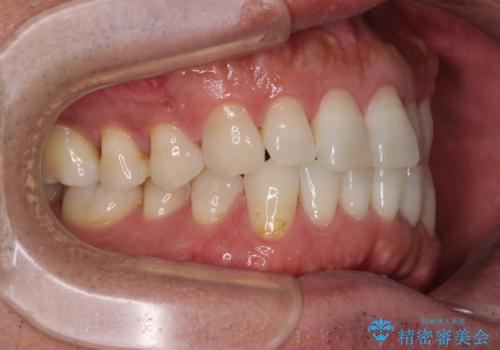

- 上顎の前歯が内側にあり、下顎のセラミッククラウンと干渉することが気になるとのことで来院された患者様です。

上顎前歯にワイヤー装置を装着し、セラミッククラウンとは干渉しないようにしながら歯列を整えることとしました。

セラミッククラウンとの干渉はすぐに改善され、歯列も整いましたが、一方で、前歯で食事が噛みにくくなり、1年近い治療期間となりました。